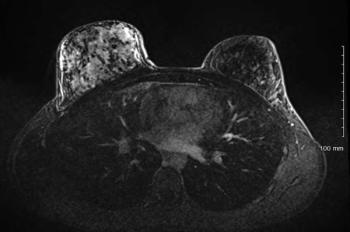

A patient with a history of thalassemia minor presents with chest pain and a cough. Imaging shows a posterior mediastinal mass. A biopsy is performed. What is your diagnosis?

A 42-year-old man presents with chest pain and a cough. Diagnostic imaging reveals a posterior mediastinal mass. Importantly, the patient has a history of thalassemia minor. A biopsy of the mass is performed.

Based on the image shown, what is your diagnosis?